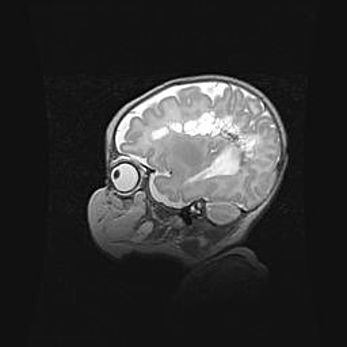

Неполная лизэнцефалия (пахигирия). Открытая гидроцефалия.

Возраст: 17 дней

Вес: 3110 г

Пол: мужской

Окружность головы: 33,5 см

Срок гестации: 35-36 недель

Лизэнцефалия—недоразвитие корковой пластинки и мозговых извилин в результате нарушения миграции нейронов коры. Поверхность мозговых полушарий гладкая. Микроскопически выявляется отсутствие нормальных слоев коры и скопление групп нейронов в подкорковом белом веществе.

Пахигирия—уменьшение числа вторичных извилин. В пораженном полушарии нервные клетки образуют толстый недифференцированный слой с неправильно расположенными нервными волокнами и группами гетеротопных клеток. Нервные клетки незрелые. Белое вещество истончено. При этом нередко аномально развит корково-спинномозговой путь.